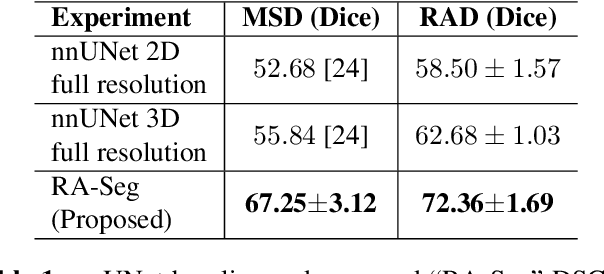

Lung cancer is a leading cause of death worldwide. Early-stage detection of lung cancer is essential for a more favorable prognosis. Radiogenomics is an emerging discipline that combines medical imaging and genomics features for modeling patient outcomes non-invasively. This study presents a radiogenomics pipeline that has: 1) a novel mixed architecture (RA-Seg) to segment lung cancer through attention and recurrent blocks; and 2) deep feature classifiers to distinguish Epidermal Growth Factor Receptor (EGFR) mutation status. We evaluate the proposed algorithm on multiple public datasets to assess its generalizability and robustness. We demonstrate how the proposed segmentation and classification methods outperform existing baseline and SOTA approaches (73.54 Dice and 93 F1 scores).